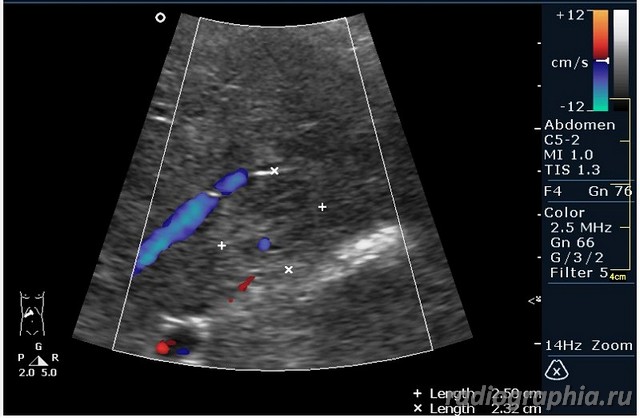

УЗИ печени. Женщина 37 лет. Жалобы на боли в эпигастрии; в печени обнаружено такое образование...

гемангиома,рядом питающий сосуд

Мне тоже нравится версия, что это - гемангиома.Нелли писал(а):гемангиома,рядом питающий сосуд